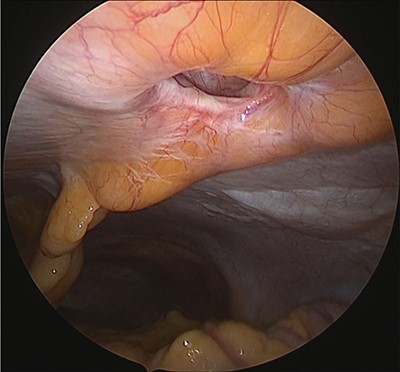

Under general anesthesia, with the patient in the lithotomy position, a 5-mm trocar was inserted into the lower right abdomen using the optical method. Observation of the abdominal cavity revealed a hernia orifice with a diameter of ~1 cm at the upper aspect of the umbilicus (Fig. 3). Two additional 5-mm trocars were inserted into the left side of the abdomen. The hernia sac was significant scarring. We then made an incision around the hernia orifice using a hook-type electrocautery electrode to expose the muscle layer (Fig. 4). The hernia sac was pushed from the surface of the body using a pean, inverted into the abdominal cavity, and excised as much as possible using electrocautery (Fig. 5). At that point, we employed the VersaOne™ Fascial Closure System to close the fascia and peritoneum at the port site.